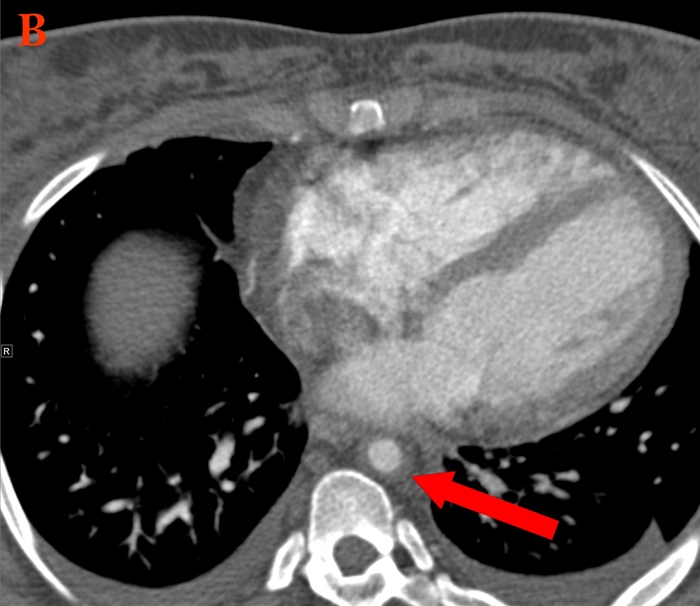

Hepatic Hydrothorax

Patients with cirrhosis and portal hypertension frequently have abdominal ascites and peripheral edema due to low albumin levels and abnormal extracellular fluid volume regulation. A small number of these patients may also develop hepatic hydrothorax, a pleural effusion not due to underlying cardiac or pulmonary abnormalities.

Hepatic hydrothorax generally results in transudative pleural effusions and is thought to occur due to small defects in the diaphragm. These defects permit peritoneal fluid to pass into the pleural space, which occurs much more commonly on the right side due to the less muscular hemidiaphragm. Patients have dyspnea, cough, pleuritic chest pain, and hypoxemia. Diagnosis involves documentation of the effusion (eg, chest x-ray) and testing to exclude other causes (eg, thoracentesis, echocardiogram).

Treatment involves salt restriction and diuretic administration. Therapeutic thoracentesis could be attempted in patients with prominent symptoms. Chest tube placement should be avoided as it can result in large-volume protein, fluid, and electrolyte losses as well as other severe complications (eg, renal failure). The definitive option for treatment is liver transplantation, although this may not be appropriate for all patients depending on other factors.